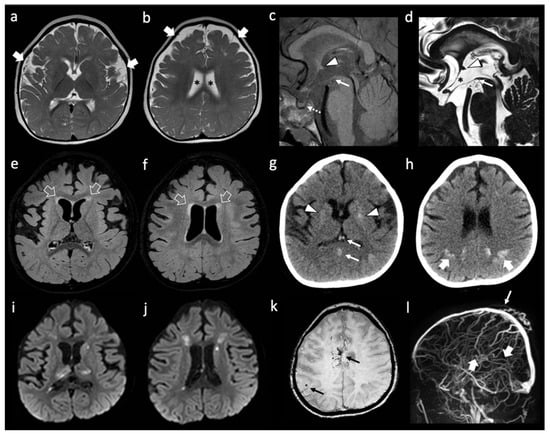

He is a Caucasian male who came to our attention at the age of 55 years because of a deep supratentorial intracerebral hemorrhage (Figure 2a) presenting with dysarthria and right hemiparesis. The past clinical history was unremarkable except for known vascular risk factors: arterial hypertension (upon medical treatment) with mild left-ventricular hypertrophy on transthoracic echocardiography, and obesity (BMI = 30). A further admission in the emergency department was registered at the age of 58 years for amaurosis fugax in the right eye. At that time, he underwent a brain MRI showing a severe SVD pattern [38] with confluent supratentorial leukoaraiosis in the bilateral parieto-occipital white matter (Figure 2b,c), chronic, silent brain infarctions with cavitate appearance involving both the superficial and deep white matter, macro-hemorrhagic scar in the left external capsule and several infratentorial and supratentorial microbleeds (Figure 2d), increased enlarged perivascular spaces mainly in the deep supratentorial compartment (Figure 2e), and significant cortical atrophy at the visual rating. Intracranial MRA sequence (Figure 2f) was significant for severe intracranial dilatative arteriopathy with prominent vertebral-basilar dolichoectasia. No systemic manifestations were present.

Figure 2.

Neuroimaging features of patient B. (a) Brain CT with acute left ICH in the external capsule. (b,c) Axial FLAIR sequences of brain MRI with leukoaraiosis and cortical atrophy. (d) T2* sequence of brain MRI with lobar microbleeds. (e) Coronal T2W sequence of brain MRI with enlarged perivascular spaces and dolichoectatic basilar artery. (f) MRA (3D reconstruction) showing the main intracranial arteries with dilatative arteriopathy.